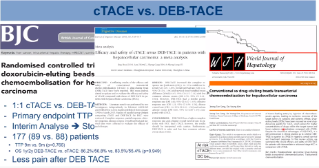

DEB-TACE Management and TACE in Combination Therapy - Dr Roman Kloeckner

Third of three podcasts on DEB-TACE with DC Bead Dr Roman Kloeckner will discuss 1) cTACE vs DEB-TACE, at minute 00:37 2) When to switch to systemic therapy, at minute 01:36 3) Combination therapy, at minute 03:03 - TACE + Ablation - TACE + TKI - TACE + Immunotherapy